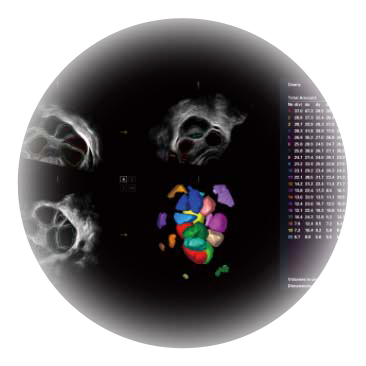

卵泡结构的自动识别和测量,可显示多组测量数据。

大角度腔内容积探头,可完整包络子宫及盆底结构,充分展示组织结构毗邻关系。